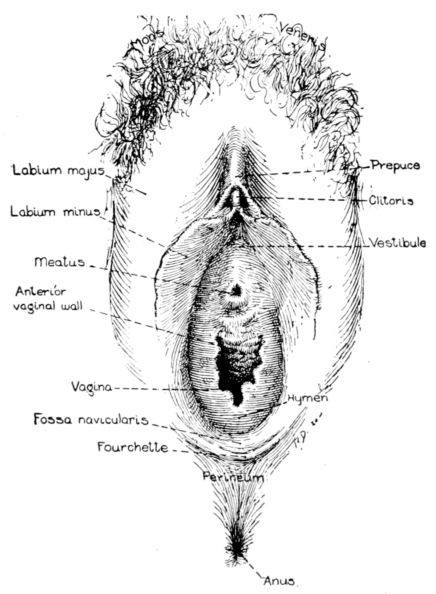

| 13. | Diagram of external female genitalia | 39 |

External Genitalia.—The vulva, or external genitalia, are situated in the pudendal crease which lies between the thighs at their junction with the torso, and extends posteriorly from the pubis to a point well up on the sacrum. (Fig. 13.)

The mons veneris is a firm cushion of fat and connective tissue, just over the symphysis pubis. It is covered with skin which contains many sebaceous glands and after puberty is abundantly covered with hair.

Fig. 13.—Diagram of external female genitalia. (Redrawn from Dickinson.)

The labia majora are heavy ridges of fat and connective tissue, prolonged from the mons veneris and extended down and back almost to the rectum, on each side, forming the lateral boundaries of the groove. They are lined with mucous membrane and covered with skin and hair, the latter growing thinner toward the perineum until it finally disappears.